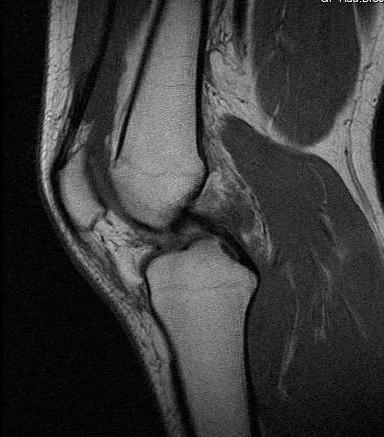

Ich war gerade im MRT wegen Problemen mit meinem rechten Knie. Hab jetzt kurz mal einen auf Dr. Google gemacht und Bilder der häufigsten Verletzungen verglichen mit meinen Bildern. Da bin ich beim vorderen Kreuzbandriss etwas aufmerkasm geworden. Das sind meine Bilder

auf dem letzten Bild sieht man mein hinteres Kreuzband ja wunderbar, es ist ja dieser dunkle "Haken", der Oberschenkel und Schienbein miteinander verbindet.

Nun aber auf dem 3. Bild sollte man doch dasselbe fürs vordere sehen? Aber ich sehe da nur die Ansätze am Schienbein?